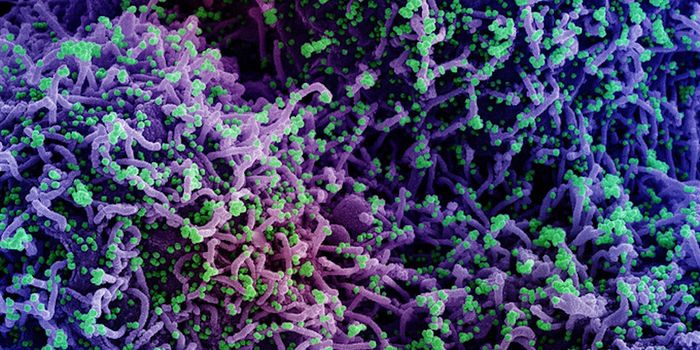

NOV 01, 2021Cell & Molecular BiologyResearchers have learned a lot about the SARS-CoV-2 virus since the start of the COVID-19 pandemic. We know that he viru ...